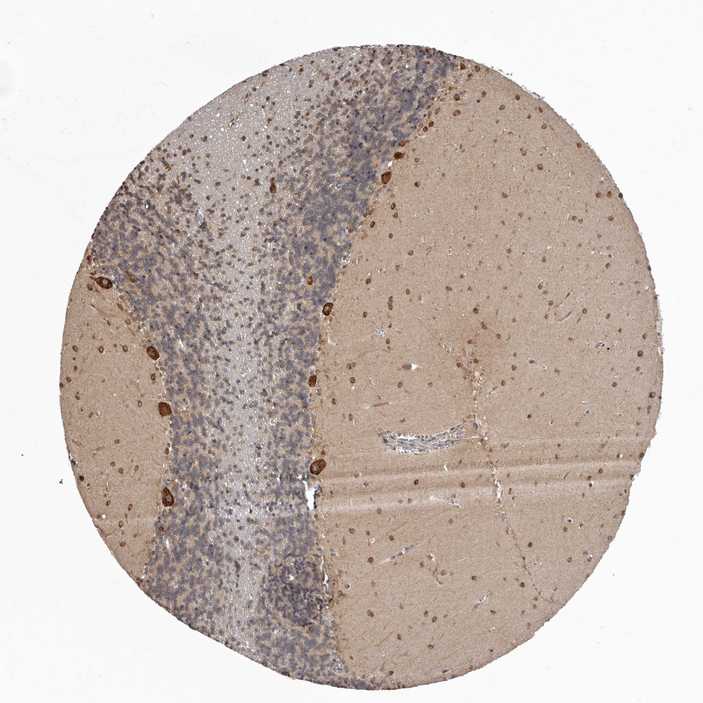

BRAIN CEREBELLUM Show tissue menu

CEREBELLUM - Expression summary

Protein expression

Cerebellumi

On the top, protein expression in current human tissue, based on all annotated cell types, is reported with the units not detected (n), low (l), medium (m) and high (h). Underneath, protein expression in each annotated cell type are reported using the same units.

Protein expression data is based on knowledge-based annotation. For genes where more than one antibody has been used, a collective score is set.

If knowledge-based annotation could not be performed for a gene, no data is displayed here. View antibody staining data further down this page.

Cells in granular layer: Low

Cells in molecular layer: Medium

Purkinje cells: High

CEREBELLUM - Antibody stainingi

Antibody staining in the annotated cell types in the current human tissue is reported as not detected, low, medium, or high, based on conventional immunohistochemistry profiling in selected tissues. This score is based on the combination of the staining intensity and fraction of stained cells.

Each image is clickable and will lead to virtual microscopy that enables deeper exploration of all samples and also displays staining intensity scores, fraction scores and subcellular localization as well as patient and tissue information for each sample.

Antibody HPA020451Antibody HPA029804Antibody HPA029805

Purkinje cells HighHighHigh

Cells in granular layer Not detectedLowNot detected

Cells in molecular layer HighMediumMedium